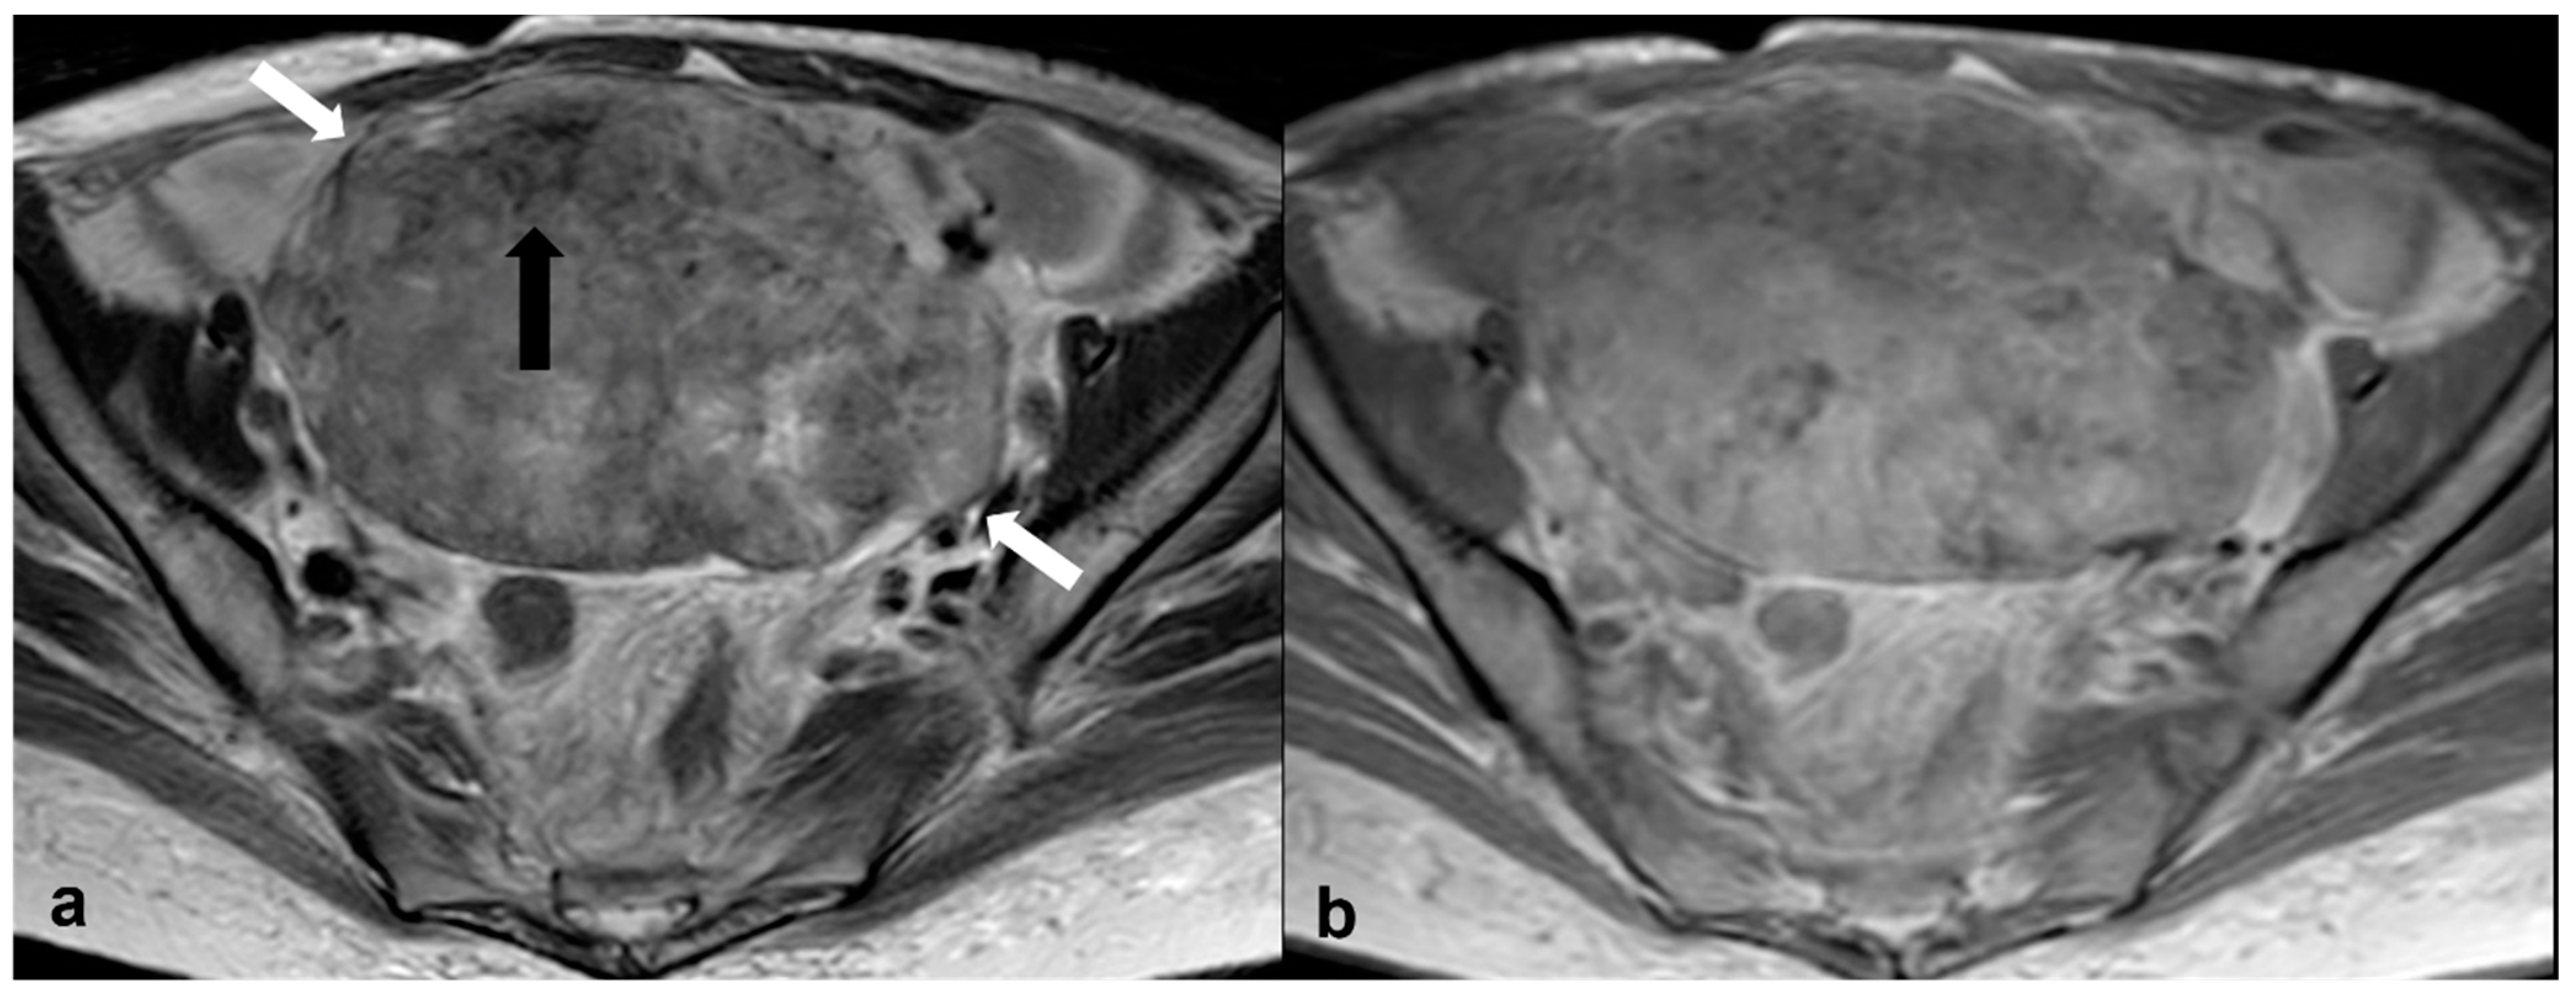

2.2.1. Cystadenofibroma

2.2.2. Fibrothecoma